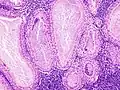

Bajo el microscopio, el tumor de Warthin tiene una apariencia muy característica. Se ven los espacios quísticos rodeados por dos hileras uniformes de células acinares con núcleos centrales y picnóticos. Estos espacios quísticos tienen epitelio que lleva el nombre de proyecciones papilares que protruyen hacia los espacios quísticos. El epitelio en cuestión está compuesto en parte por un rico estroma linfoide con formación germinal en el centro.[4]

- Histopatología del tumor de Warthin en la glándula parótida.

- Otra vista de la imagen anterior.

- Mayor magnificación de la imagen anterior.